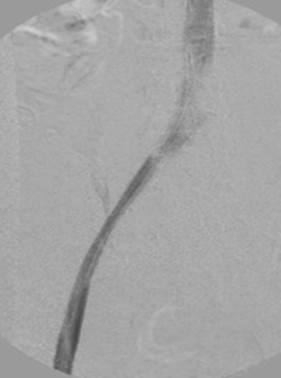

Venograma en posición de decúbito prono donde se muestra un trombo agudo oclusivo que va de la vena poplítea derecha hasta el filtro de VCI.

Venografía posterior a la trombólisis venosa bilateral y la trombectomía; eliminación del trombo tras una sola pasada del catéter DVX de AngioJet (técnica Rapid Lysis; 25 mg de tPa @1 mg/ml + 225 cc de solución salina normal = solución de 250 cc).

Tras la inserción del catéter DVX de AngioJet, la aspiración y la colocación de stents de 14 mm x 150 mm. Resulta en un trombo en la pierna derecha de aproximadamente 2 meses de antigüedad. Se requiere más ATP de la vena ilíaca externa derecha.